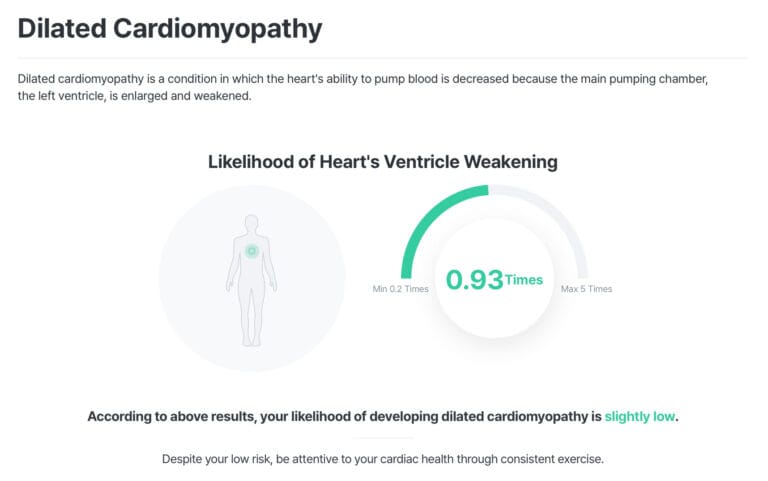

At MyDNA, we believe knowledge is power. Predictive DNA testing provides personalised insights into your genetic predisposition for heart disease and related conditions. Here’s how our DNA testing service empowers individuals: